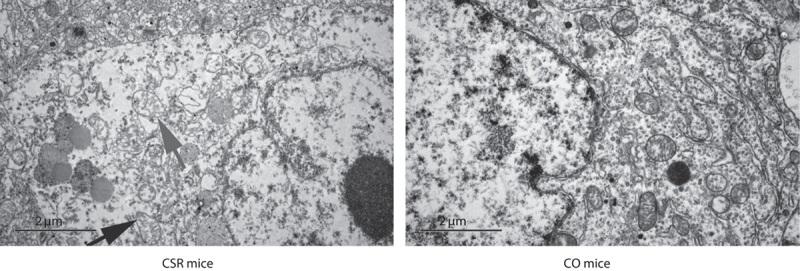

Mitochondrial dysfunction induced by mitochondria-related β-amyloid (Aβ) accumulation is increasingly being considered a novel risk factor for sporadic Alzheimer's disease pathophysiology. The close relationship between chronic sleep restriction (CSR) and cortical Aβ elevation was confirmed recently. By assessing frontal cortical mitochondrial function (electron microscopy manifestation, cytochrome C oxidase concentration, ATP level, and mitochondrial membrane potential) and the levels of mitochondria-related Aβ in 9-month-old adult male C57BL/6J mice subjected to CSR and as an environmental control (CO) group, we aimed to evaluate the association of CSR with mitochondrial dysfunction and mitochondria-related Aβ accumulation. In this study, frontal cortical mitochondrial dysfunction was significantly more severe in CSR mice compared with CO animals. Furthermore, CSR mice showed higher mitochondria-associated Aβ, total Aβ, and mitochondria-related β-amyloid protein precursor (AβPP) levels compared with CO mice. In the CSR model, mouse frontal cortical mitochondrial dysfunction was correlated with mitochondria-associated Aβ and mitochondria-related AβPP levels. However, frontal cortical mitochondria-associated Aβ levels showed no significant association with cortical total Aβ and mitochondrial AβPP concentrations. These findings indicated that CSR-induced frontal cortical mitochondrial dysfunction and mitochondria-related Aβ accumulation, which was closely related to mitochondrial dysfunction under CSR.